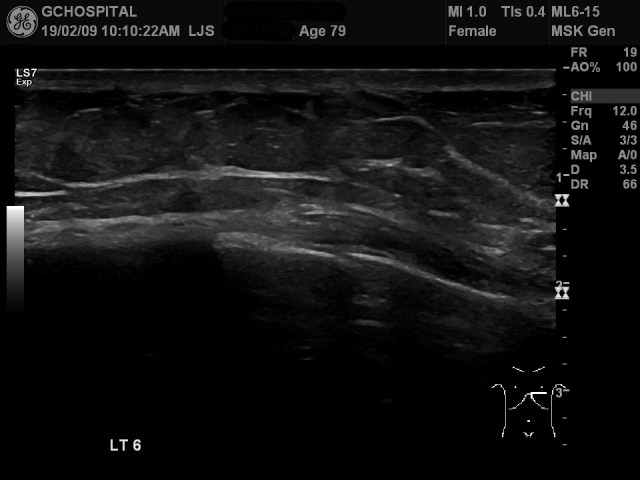

6번째 늑골에서는 골절이 훨씬 더 뚜렷하고, bone fragment가 별도로 힘을 주지 않은 상태에서도 확실히 벌어져 있습니다. 앞서 5번째 늑골에서도 힘을 줬을 때 많이 움직이고 있었기 때문에, 5,6번 늑골 모두 완전골절입니다.